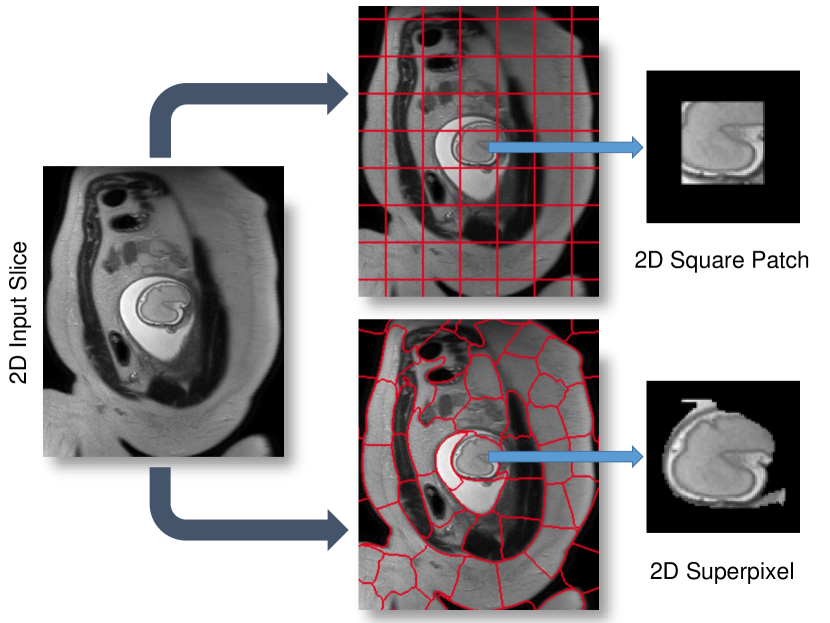

SVR-based motion compensation methods make use of the assumption that rigid regions, e.g., brain and thorax, of 2D input slices deforms rigidly, where a global 3D volume is reconstructed by iteratively registering these 2D input slices. We propose to increase the granularity of the input data by using 2D data patches of arbitrary shape instead of whole slices for SVR reconstruction. We explore square patches and dilated superpixels [27] for the definition of the patch shape. Superpixels provide a method to define semantically meaningful regions while reducing the required data redundancy and computational overhead.

In the simplest, naïve case the shape of is square, and defined via its size and stride . Such definition is generally applicable to any kind of oversampled motion corrupted data. If and are fixed, no prior knowledge about the data is assumed. However, ideally each corresponds to a meaningful subregion of the volume in which motion can be characterized as rigid. Typically, the square patches are overlapping to provide redundant representations of the same locations. Such approach is computationally expensive with increasing number and patch size and additional consideration must include the inherent trade-off between and the assumption of it containing rigid motion.

An alternative to naïve shape definitions of is to find correlation between voxel locations and its neighbors, which can be found by unsupervised image segmentation techniques such as superpixels (SP) [27]. These techniques allow for obtaining similar-sized segments from local intensity information (see Fig. 5) instead of employing dense sampling of overlapping patches, enabling the image reconstruction with fewer but more useful data blocks. Further, reducing the total amount of required data blocks for reconstruction lowers the computational overhead, positively impacting the overall run-time. Additionally, larger rigid areas require less computational effort for image registration and super-resolution, and more importantly less dependency on inherent image data parameters (e.g., voxel spacing, organ size, subject size).

While there are several techniques for generating SP in the literature [28, 29, 27], a fast and efficient SP approach is desirable for the clinical practice. Simple linear iterative clustering (SLIC) [27] allows to obtain regular SP based on minimizing the distance between the centroids of SP with an initial step size . D is defined as:

where and are the intensity and spatial Euclidean distances that are controlled by an adaptive compactness parameter for each SP. Similarly to naïve shape definitions, we can define the initial size of the SP as and its dilation size .